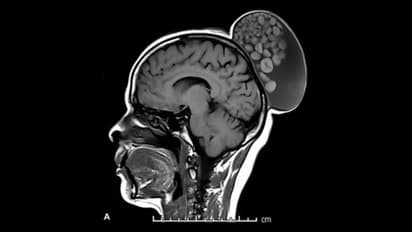

எம்ஆர்ஐ ஸ்கேன் செய்ததில், அவளது தலையின் பின்பகுதியில் ஒரு சதைப்பற்றுள்ள வளர்ச்சி இருப்பது தெரியவந்தது. வளர்ச்சியை அகற்ற அறுவை சிகிச்சையின் போது, திரவம், முடி, கொழுப்பு மூலக்கூறுகள் மற்றும் கெட்டியான வெளிப்புற விளிம்புகள் கொண்ட கெரட்டின் பந்துகள் ஆகியவற்றால் நிரப்பப்பட்டிருப்பதை மருத்துவர்கள் கண்டறிந்தனர்.